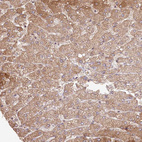

Immunohistochemical staining of human cerebral cortex, liver, skin and testis using Anti-HAL antibody HPA038547 (A) shows similar protein distribution across tissues to independent antibody HPA038548 (B).